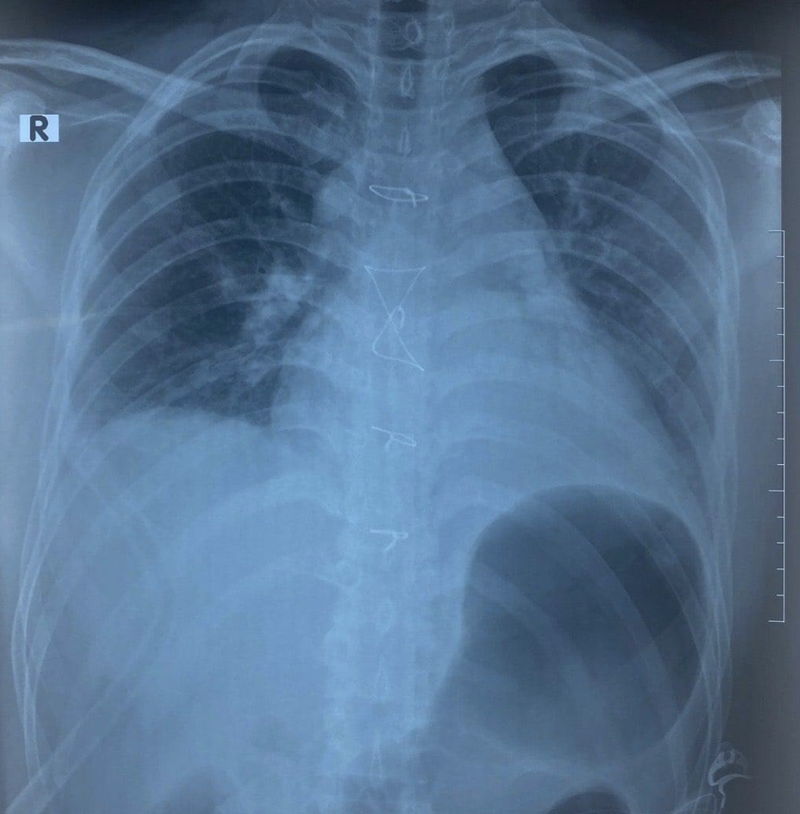

Bệnh nhân vào Bệnh viện Trung ương Quân đội 108 trong tình trạng khó thở với một vết bầm tím nhỏ ở ngực, kèm theo tiếng tim nghe hơi mờ. Siêu âm tim, các bác sĩ phát hiện bệnh nhân có dịch trong khoang màng tim. Chụp CT thấy bệnh nhân bị vỡ xương ức, gãy cung trước xương sườn 7,8 bên phải, tràn dịch khoang màng tim và màng phổi phải, vỡ gan độ 3.

Ảnh chụp X-quang của bệnh nhân (Ảnh: BVCC) |